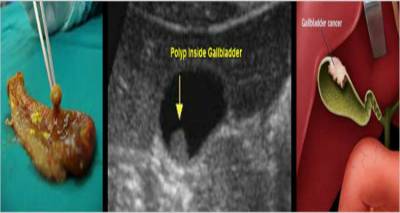

Γράφει ο Δρ Γιώργος Σάμπαλης

Γενικός Χειρουργός-Λαπαροσκόπος

Διευθυντής Χειρουργός Ευρωκλινικής Αθηνών

www.sambalis.gr